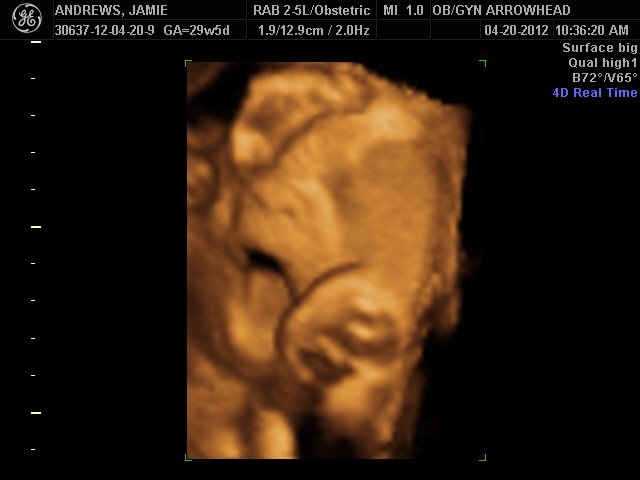

We offer complimentary 3D/4D Ultrasounds to all our OB patients around 30 weeks! The following photos are some examples of our work, shown with permission from our patients.